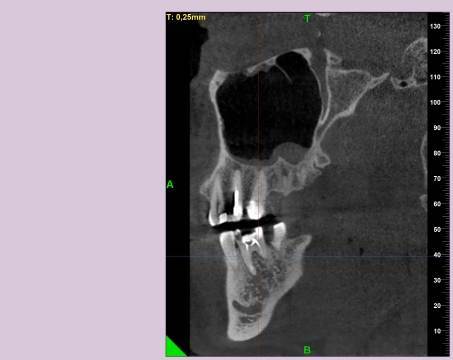

КТ от 04.03.2024

69273_3.jpg.f56a31dc1d8d53085767a9a52915128c.jpg69273_4.jpg.f9ec255bedbdb9fde8159318d3cb1fd9.jpg69273_5.jpg.36a7a942d403dd2eb062e5a4b2b58a52.jpg69273_6.jpg.492d3fbca3808fbdf58c86056b2fe0c3.jpg69273_7.jpg.f9bfdd5d593504dc7bd3710ece18aa4f.jpg69273_8.jpg.853e2342e6f2329a2e89c8939c2aad6f.jpg69273_11.jpg.e495813d50bf007f7165bf5f5dfec4b3.jpg69273_12.jpg.49b3cf66b4dd26b5cd68a91b2684e402.jpg69273_13.jpg.5d61b621b8e8b2c473ad6a8aca42502d.jpg

КТ от 28.05.2024

28_05.24(2).jpg.0ffa1febe861106733e1de830afbe6f4.jpg28_05.24-1(2).jpg.9c45d7be16aeed505bd413ce9bc6e69e.jpg28_05.24-2.jpg.a728a7d7e6213c1c8302b43adc89e4d0.jpg28_05.24-4(2).jpg.ac43f3448a3988c7006f74e1d0ce09da.jpg28_05.24-6(2).jpg.dd1fd85c6cc0fcd3d43bd9e71fc0d616.jpg28_05.24-8(2).jpg.885c8cb905445e9308f124fb9e5c616b.jpg28_05.24-9(2).jpg.6cceaaaa1b56d0967482c87b951fbe2d.jpg28.5.24-5(2).jpg.b2d79427a16769c9fd4f0d0911a9db8f.jpg28.5.24-7(2).jpg.f6c17f9820e72dc2708955a65a190b57.jpg28.0524-3(2).jpg.0aa9f153071766a340b428158a94ade8.jpg